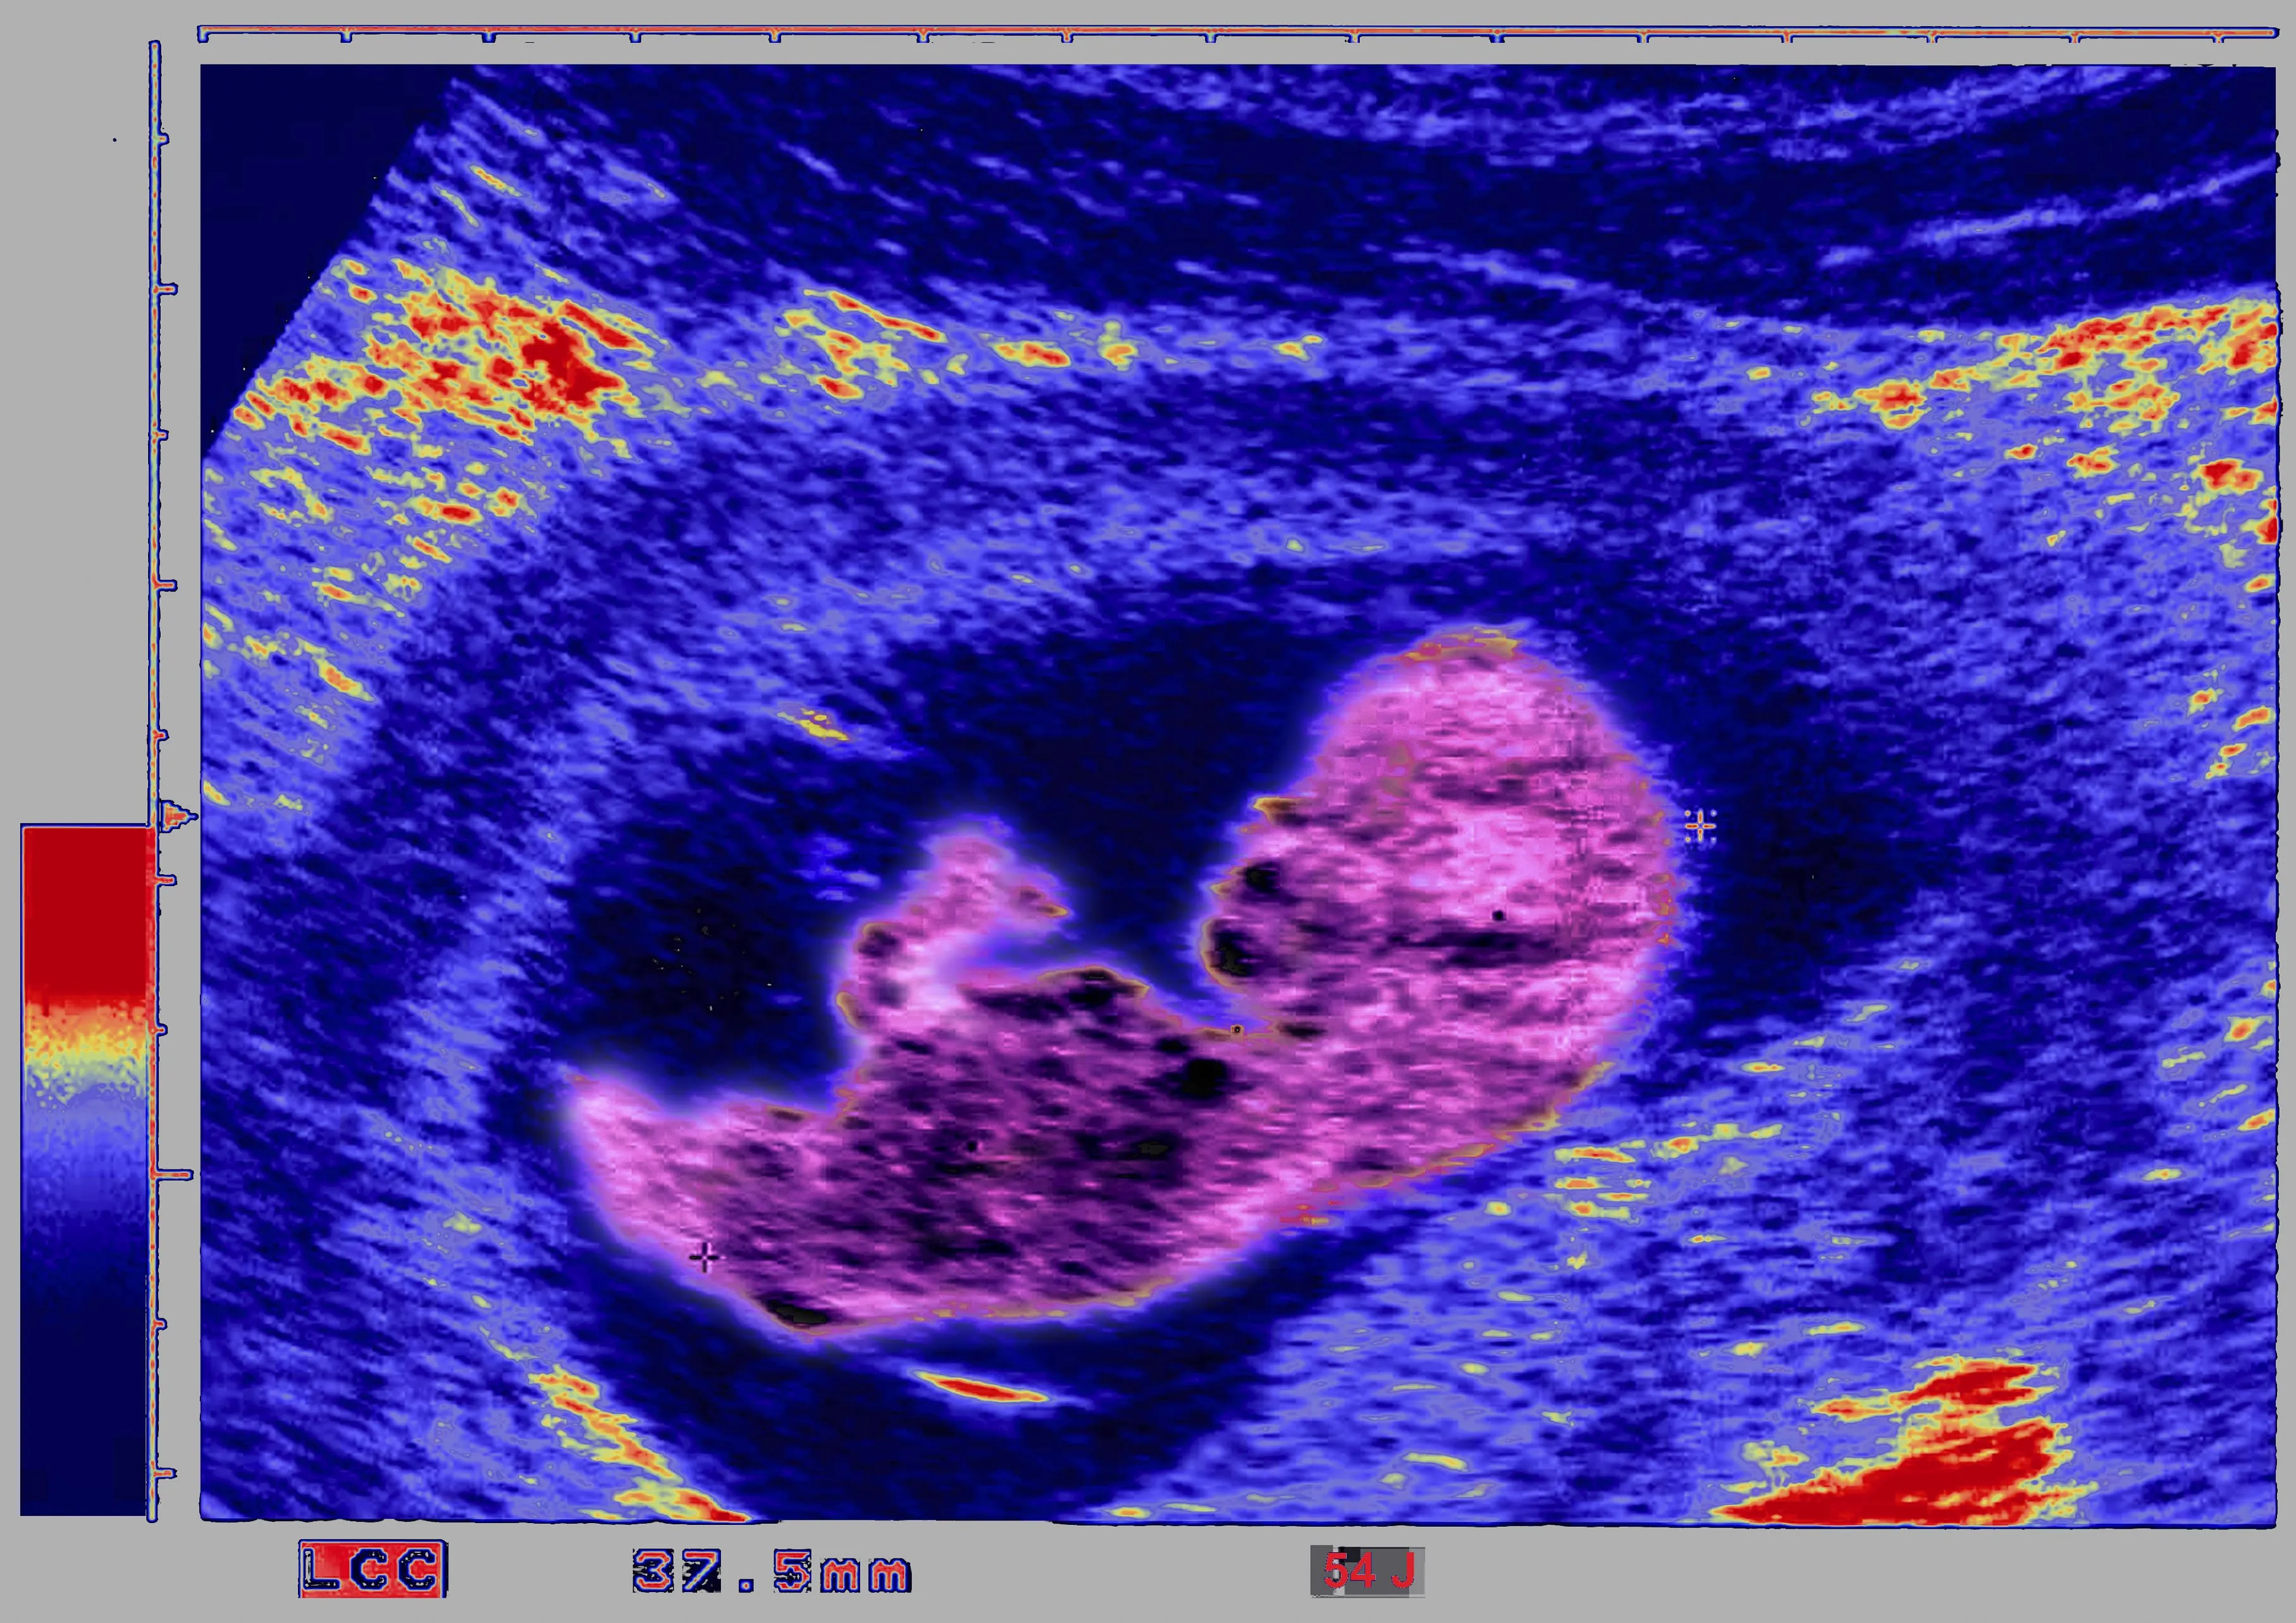

Source: BSIP/Universal Images/Getty Images